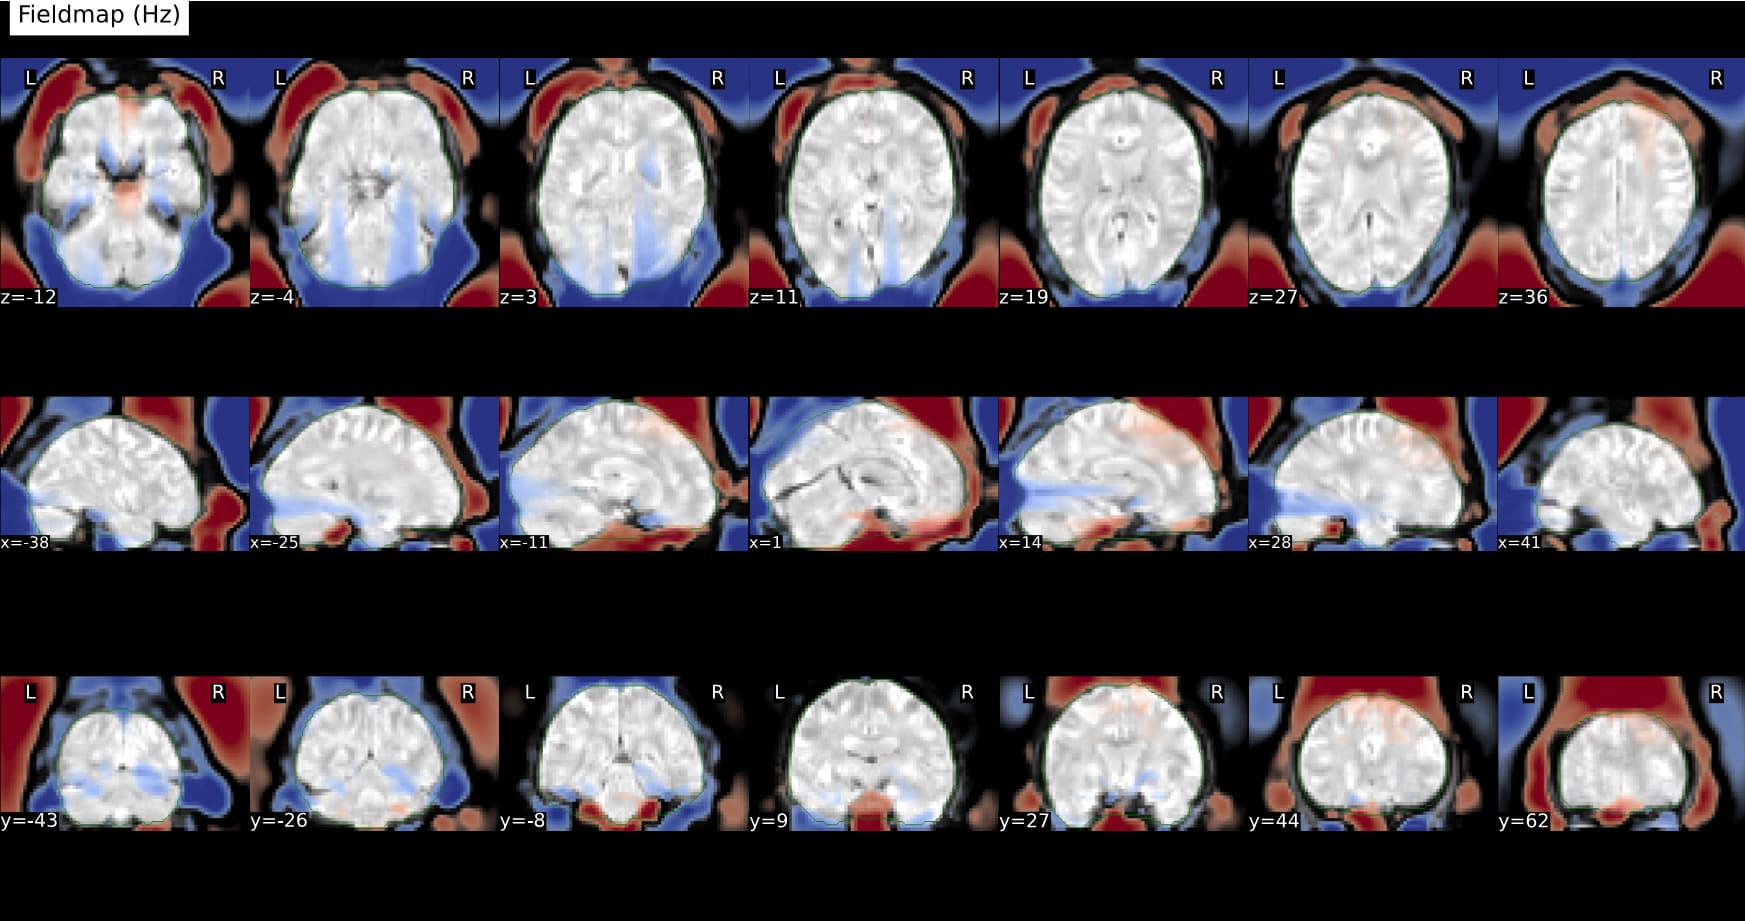

fmap/folder: the fieldmap in Hz and undistorded magnitude image generated by topup run by SYNB0-DISCO. In that case FMRIPREP would use the Direct B0 mapping method for SDC. That could work! To be tested.